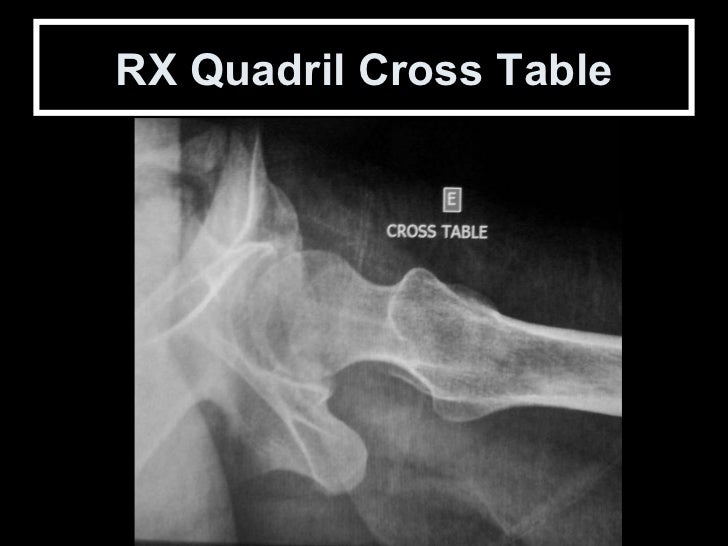

Cross Table ou Arcelin Assim como na incidência de Ducroquet, o colo femoral é visto em perfil permitindo uma boa avaliaçã...

RX Quadril Cross Table

66. 68. Cross Table ou Arcelin Assim como na incidência de Ducroquet, o colo femoral é visto em perfil permitindo uma boa avaliação do colo e da porção anterior da transição cabeça colo femoral. Para obtenção de imagem com qualidade suficiente para o diagnóstico, deve-se utilizar uma técnica apurada de 85 KV com 60 MAS no bucky portátil

67. 69. RX Quadril Cross Table